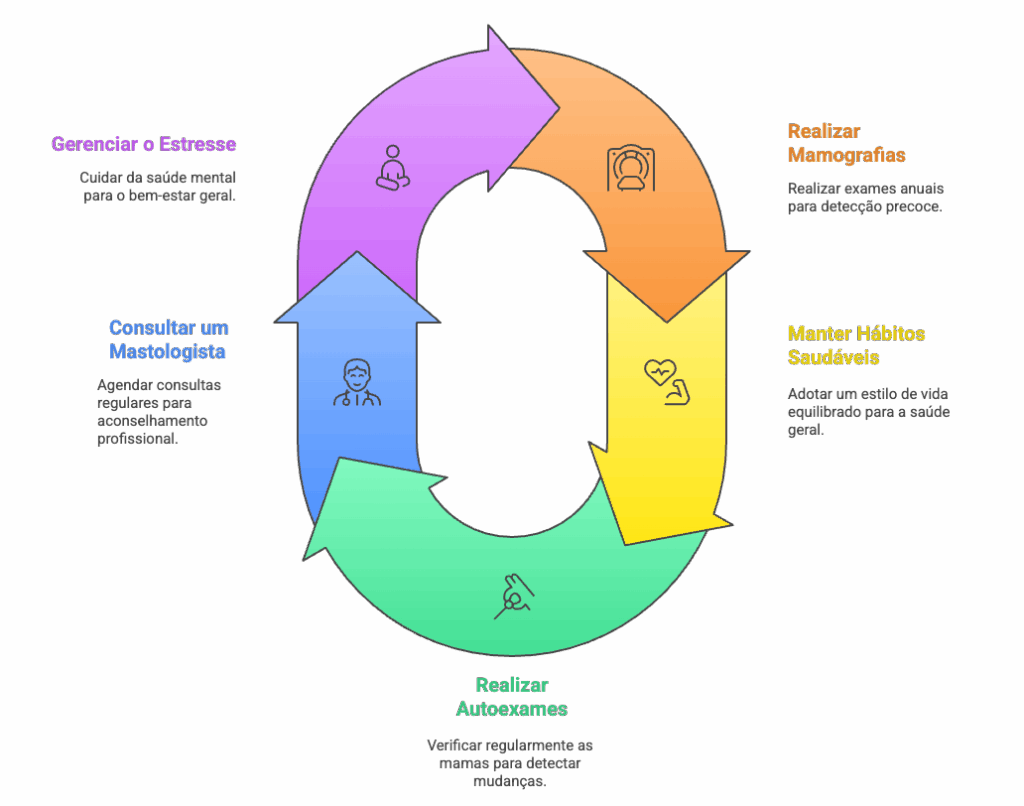

Embora não possamos prevenir completamente o aparecimento de calcificações (já que fazem parte do processo natural de envelhecimento), podemos manter nossa saúde mamária em dia:

- Realize mamografias anuais após os 40 anos (ou conforme orientação médica)

- Mantenha hábitos saudáveis: alimentação equilibrada, exercícios regulares, controle do peso

- Conheça sua mama: realize o autoexame mensalmente

- Mantenha consultas regulares com seu mastologista

- Gerencie o estresse e cuide da saúde mental